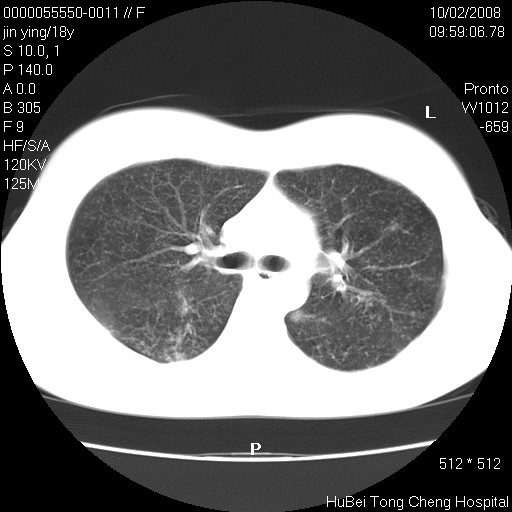

患者 女,18y。发热十余天,伴咳嗽。pe:t39⒈℃,bp 110/80mmhg,p 86次/min。神清,精神欠佳。双肺可闻及少许湿罗音。既往史不详。

临床诊断:肺部感染?

胸部ct轴位平扫(层厚10mm,螺距1.5,重建间隔10mm),图像如下: